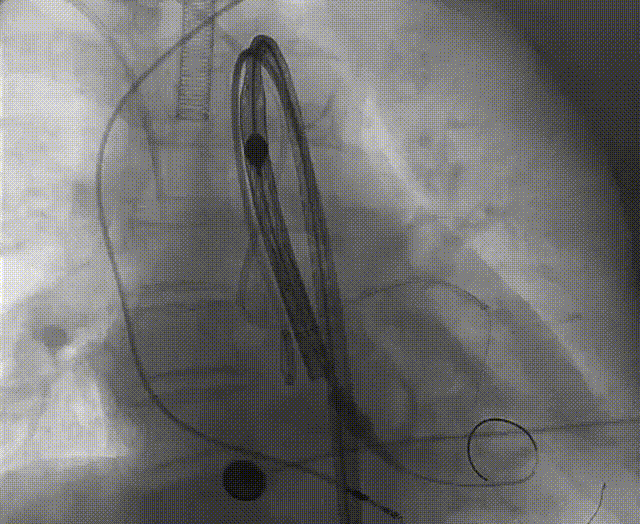

手术流程概括

22球囊扩张,无明显腰增,无造影剂泄露。

瓣膜初始零位释放,释放后位置尚可,决定完全释放。

瓣膜释放后有瓣周漏显示决定进行球囊后扩。

后扩后形态良好,瓣膜展开充分,轻微瓣周漏。